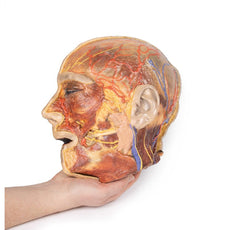

3D Printed Brain Hemisection

This 3D model is a midsagittal hemisection through a whole brain, preserving the right side anatomy and deep brain

structures and spaces visible in the midline. In lateral view, the right cerebral and cerebellar hemispheres are

covered in the arachnoid mater. In the midline view, the brain regions from the cerebrum to the medulla oblongata

are preserved. Centrally, the third ventricle is opened, with an intact septum pellucidum superiorly positioned and

obscuring the lateral ventricles within the cerebral hemisphere. On the inferior margin of the third ventricle both

the right mamillary body and right optic tract can be observed, whereas posteriorly the cerebral aqueduct can be

observed extending across the midbrain between the tectum and tegmentum towards the fourth ventricle (between the

cerebellum and pons). The cerebellum is separated from the occipital lobe by a preserved portion of the tentorium

cerebelli, and in cross-section the cerebellar cortex helps form the prominent arbor vitae.

A series of arterial

branches have been false coloured to contrast their course across the preserved brain structures. In the midsagittal

view the anterior cerebral artery courses from around the corpus callosum to supply the cingulate gyrus and other

midline cortical regions. The base of the middle cerebral artery can be seen passing deep between the temporal and

frontal lobes, with the posterior communicating artery connecting it to a small remnant of the posterior cerebral

artery. Adjacent to the posterior cerebral is the superior cerebellar artery, extending laterally to pass between

the temporal lobe and the cerebellum before passing deep into the transverse fissure.